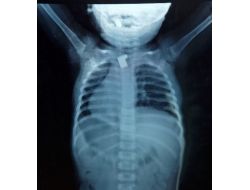

YEMEK BORUSUNA TAKILI ANAHTAR PARÇASI BULUNDU